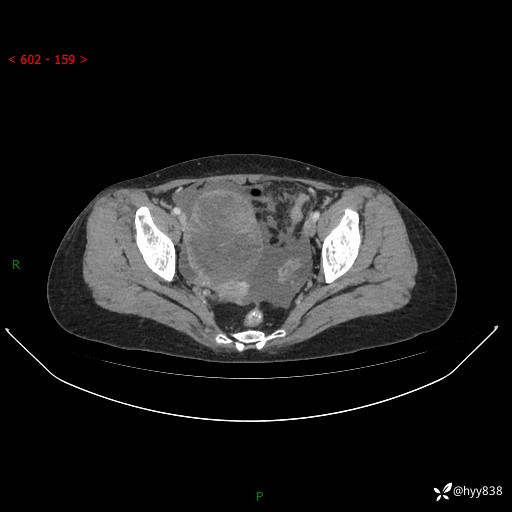

老年女性,尿频2月。超声发现盆腔囊实性占位,CT能否明确诊断---结果公布

现病史:患者绝经3-4年,期间无阴道出血及排液。患者近2月感尿频,自行口服中药治疗,症状无明显缓解。2024-4-25日于我院门诊就诊,行阴道彩超示:子宫肌瘤(大小约12*10mm,后壁),子宫右前方囊实性占位性病变(大小约126*82mm肿块声像,边界尚清,以无回声为主,可见范围约84*27mm稍高回声),内膜3mm。建议手术治疗。门诊以“卵巢囊肿”收入院。 病程中精神、食欲、睡眠可,大小便正常,体重体力无明显变化。

腹盆CT平扫

增强